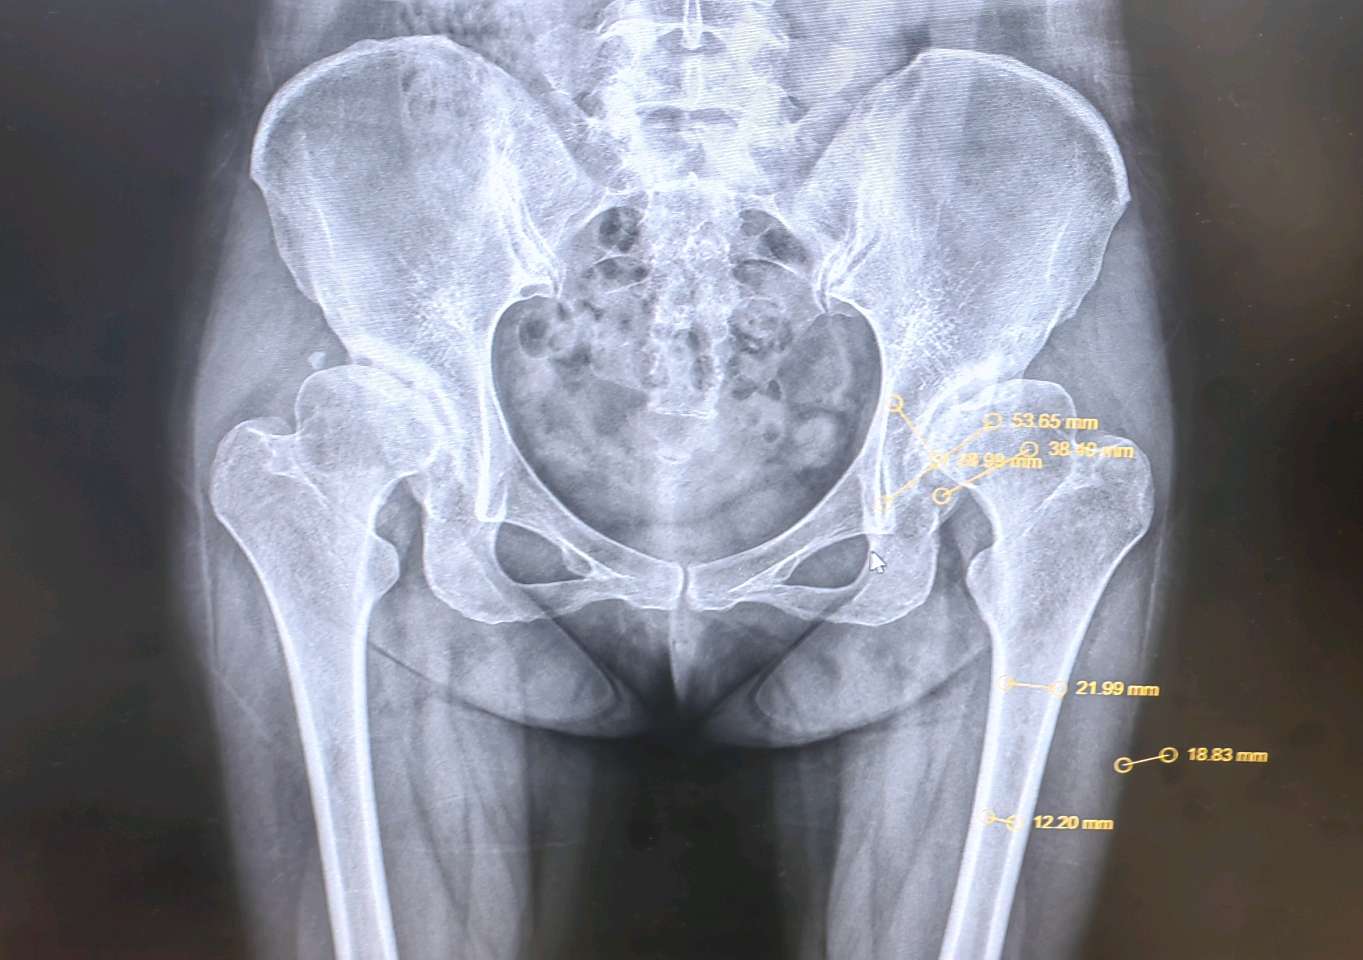

X光片、CT或MRI等影像学检查为手术决策提供了客观依据。当出现以下表现时,说明关节软骨已经严重磨损,退行性变已进入晚期:

1. 关节间隙显著狭窄或消失:这是软骨几乎完全磨光的直接证据,导致骨头与骨头直接摩擦(“骨对骨”)。

2. 出现大量骨赘(骨刺):关节为增加稳定性而代偿性增生,但会加剧疼痛和僵硬。

3. 软骨下骨硬化或囊性变:骨头因长期异常受力而变得致密(硬化)或出现囊性空洞,这常常是疼痛的来源之一。

4. 继发性骨关节炎:髋臼发育不良的最终结果就是导致髋关节过早地出现严重的骨关节炎。